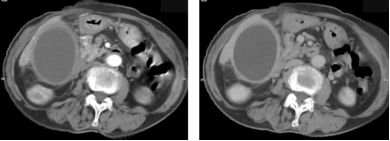

慢性胰腺炎CT表现:胰腺体积大小可正常,也可增大或缩小,改变可呈局限性或弥漫性。弥漫性萎缩也见于糖尿病病人及老年人;胰管扩张:多显示不同程度扩张,可呈管状或串珠状;胰管结石和胰实质钙化。

截屏2022-10-06 18.56.53